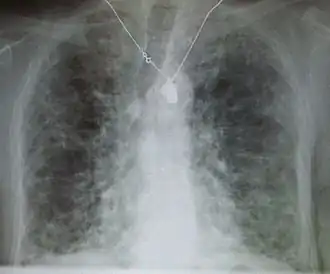

A chest x-ray is 63% sensitive and 93% specific for ILD.[10] With advances in computed tomography, CT scans of the chest have supplanted lung biopsy as the preferred diagnostic test for ILD. A thoracic CT scan is 91% sensitive and 71% specific for ILD.[10] In higher income countries, less than 10% of people with ILD undergo a lung biopsy as part of the diagnostic evaluation.[16]

Chest radiography is usually the first test to detect interstitial lung diseases, but the chest radiograph can be normal in up to 10% of patients, especially early in the disease process.[19][20]

High-resolution CT of the chest is the preferred modality and differs from routine CT of the chest. Conventional (regular) CT chest examines 7–10 mm slices obtained at 10 mm intervals; high resolution CT examines 1–1.5 mm slices at 10 mm intervals using a high-spatial-frequency reconstruction algorithm. The HRCT therefore provides approximately 10 times more resolution than the conventional CT chest, allowing the HRCT to elicit details that cannot otherwise be visualized.[19][21]

Radiologic appearance alone, however, is not adequate and should be interpreted in the clinical context, keeping in mind the temporal profile of the disease process.[19]